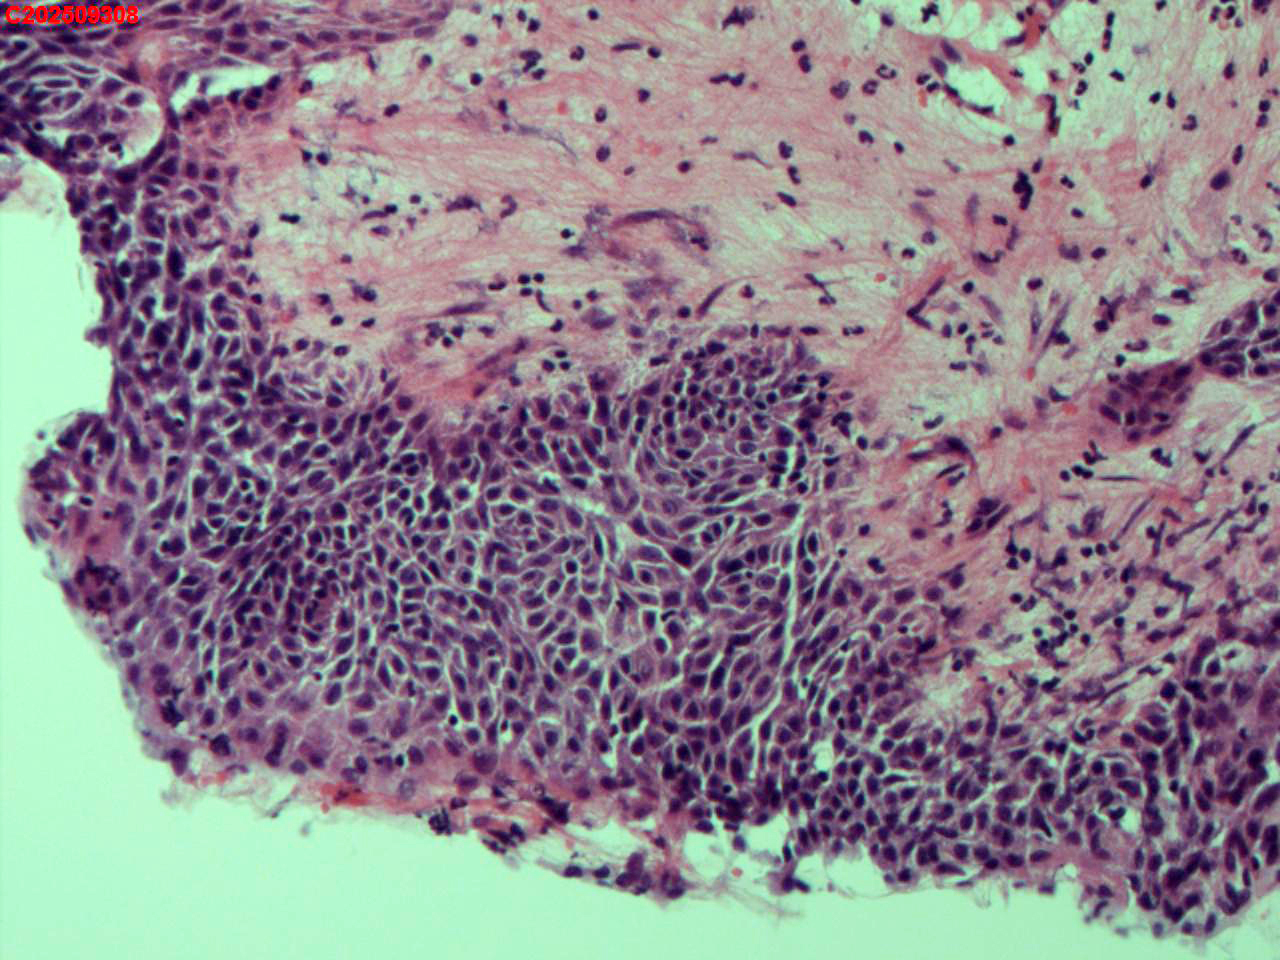

纤支镜咬检

肺结核、气管结核?

胸部CT:左肺多发病变及空洞考虑结核,请结合其他相关检查。右肺上叶小点状钙化灶。左肺门增大。

纤支镜:肉芽增生

送检粘膜鳞状上皮增生伴炎性渗出物及坏死物,建议做抗酸染色排除结核